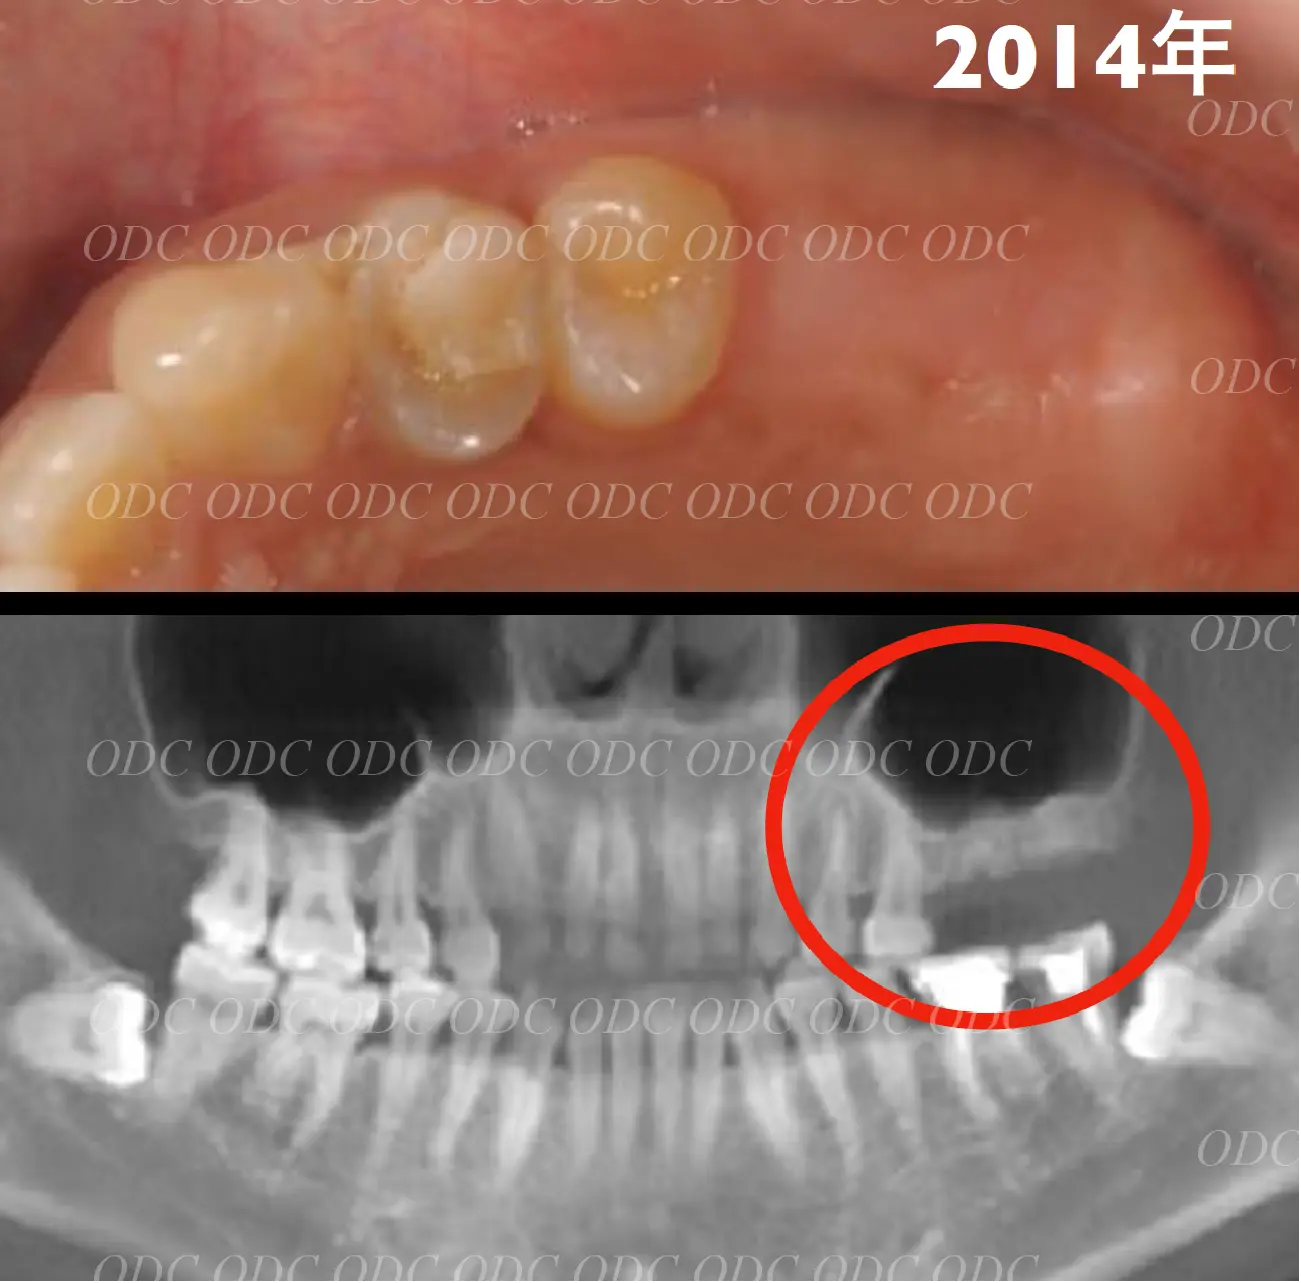

前歯部少数歯欠損症例

2014年、前歯1本欠損でインプラント治療を希望されて来院されました。

サージカルガイドを作成しインプラント埋入を行っていきました。

骨造成 結合組織移植等を行いながら最終印象を行っていきました。

最終補綴装着後の口腔内写真です。自然な仕上がりにご満足頂いております。